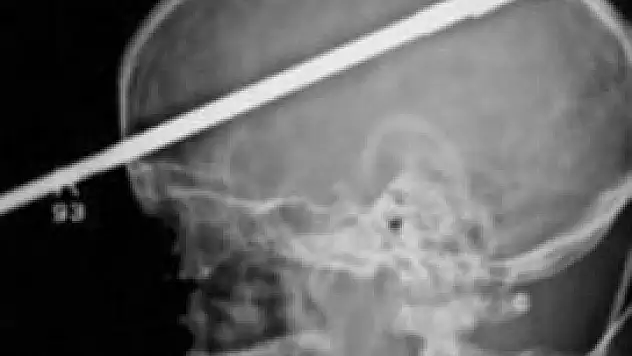

İnanılmaz kurtuluş!